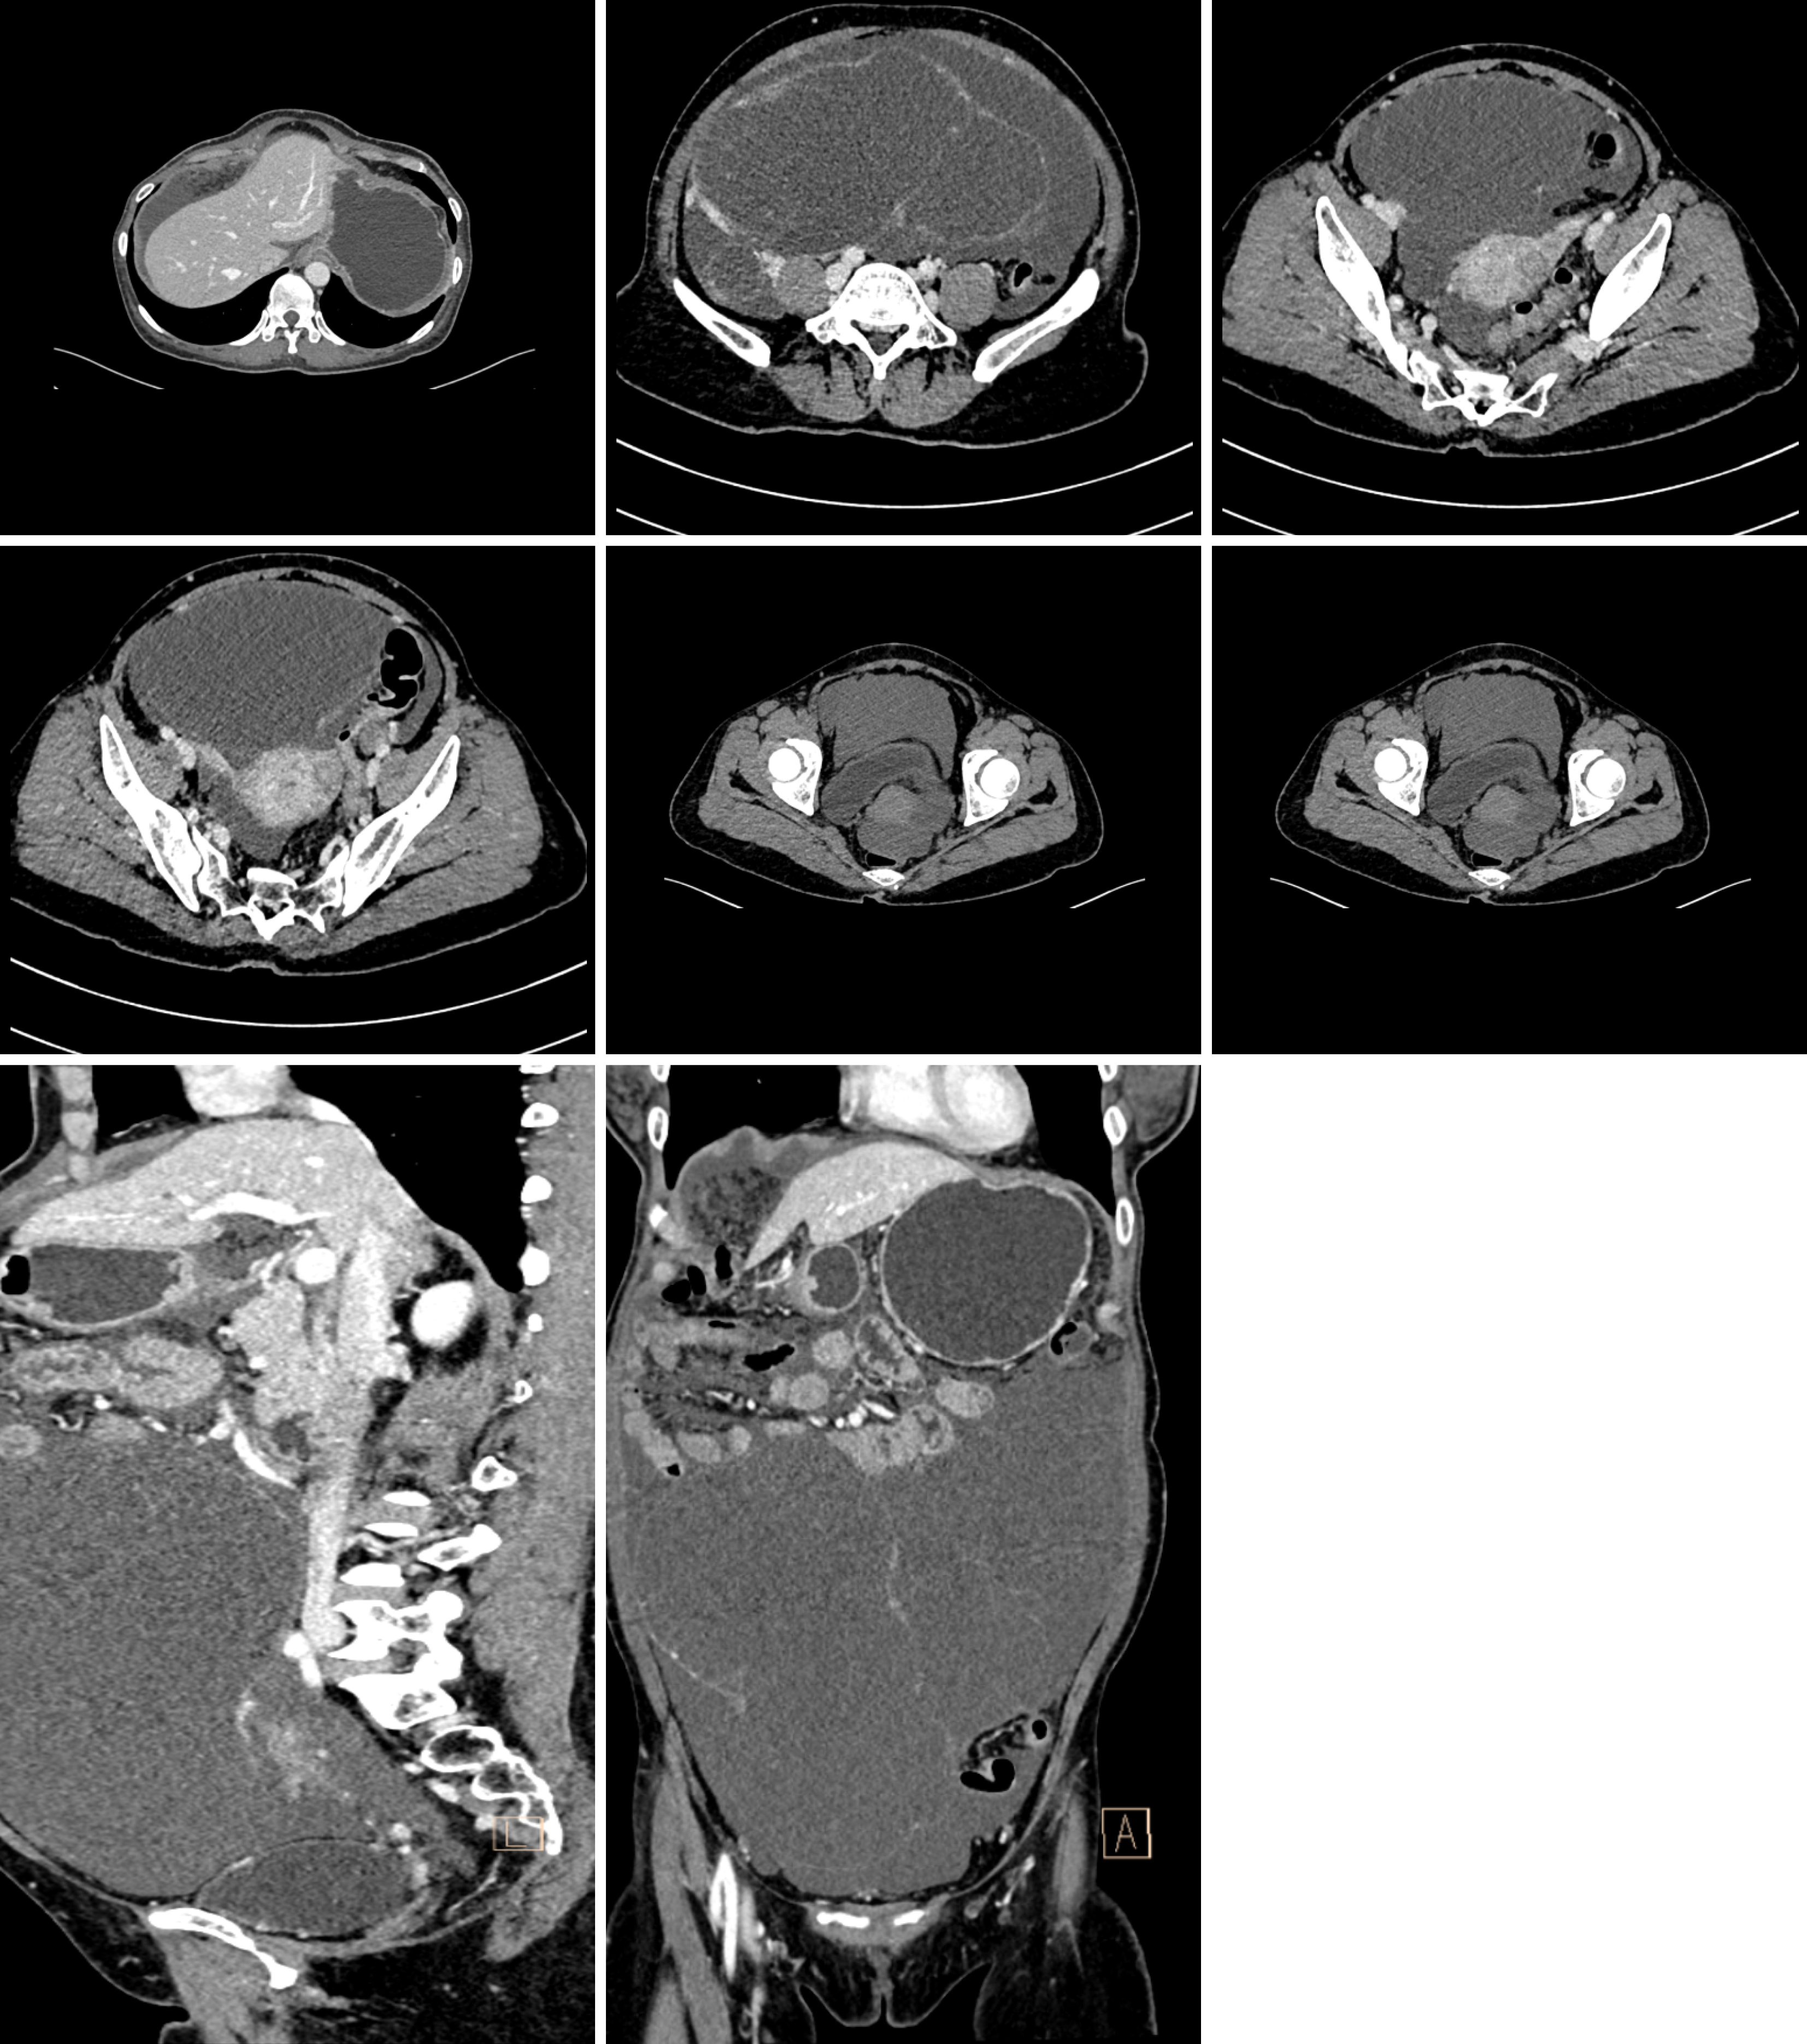

Figure 2 Computed tomography scan of abdomen with contrast shows the lesion before treatment.